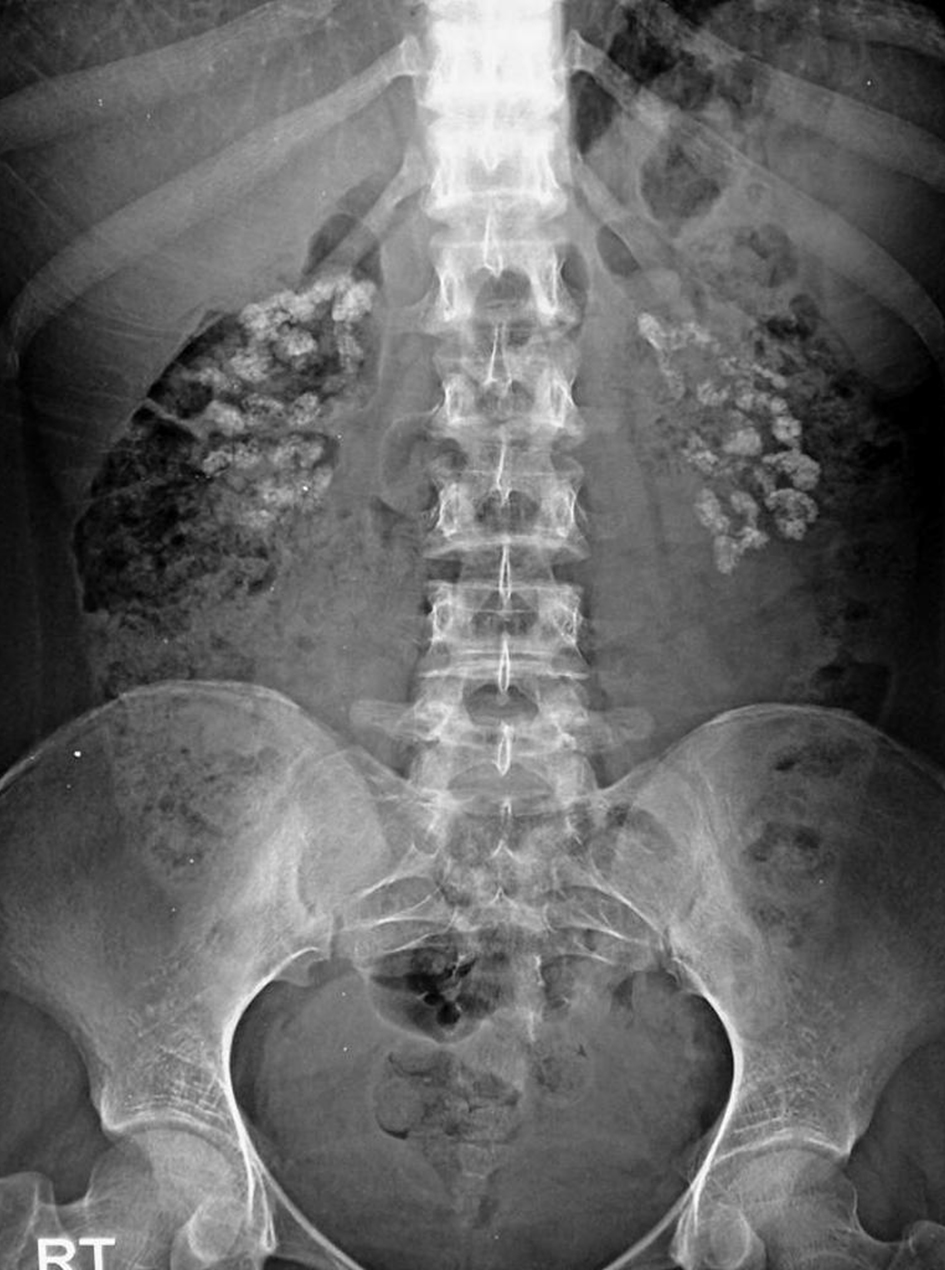

A 20-year-old African woman presented to Dalal Jamm Hospital for paralysis of four limbs. The physical examination showed paraplegia and arrhythmia on cardiac auscultation. Vital signs were significant for blood pressure 120/80 mm Hg, pulse 88 beats/min, temperature 36.6 °C, weight 69 kg and diuresis 3 L/24 h. This patient had a long history of hospitalization in the neurology department for paraplegia secondary to the hypokalemic crisis. She had no family history of kidney disease or sickle cell disease. The Schirmer test was positive. Laboratory investigations revealed serum: K+: 1.4 mmol/L, Na+: 134 mmol/L, Cl-: 113 mmol/L; urine studies: Na+: 250 mmol/24 h, K+: 53 mmol/24 h, Cl-: 254 mmol/24 h; urinary urea 5.2 g/24 h, urine creatinine 139 mg/L, glucose 0.99 g/L, urinary osmolarity 202.6 mmol/L, plasma osmolarity 290.3 mmol/L, the transtubular potassium gradient (TTKG) 5, serum magnesium 23 mg/L, alkaline reserves 15.69 mmol/L, the plasma anion gap 9.3, urine anion gap 10, urine pH 7.5, serum creatinine 7 mg/L, calcium 90 mg/L, phosphorus 25 mg/L and urine calcium 187 mg/24 h. Abdomen X-ray showed nephrocalcinosis (Fig. 1). The diagnosis of DTA1 complicated by hypokalemia was made. The electrocardiogram showed atrial extrasystoles. The hemogram showed hemoglobin 12.4 g/dL, white blood cells 4,080/mm3, lymphopenia at 900/mm3 and platelets 371,000/mm3. Thyroid-stimulating hormone (TSH) and C-reactive protein were normal. Electrophoresis of serum proteins showed polyclonal hypergammaglobulinemia. Anti-nuclear antibodies were positive at 380 with speckled fluorescence. The native anti-DNA antibodies were negative. The anti-SSA was positive. The anti-SSB was negative. The accessory salivary gland biopsy showed grade 4 lymphocytic sialadenitis from Chisholm and Mason (Fig. 2). We made the diagnosis of primary SS because she had a score according to 2016 American College of Rheumatology/European League Against Rheumatism Classification Criteria for Primary Sjogren’s Syndrome of 7 (The Schirmer test positive (score = 1), Labial salivary gland with focal lymphocytic sialadenitis, focus score of ≥ 1 foci/4 mm2 (score = 3), anti-SSA/Ro positive (score = 3)) and she had no exclusion criteria. Primary SS was identified as the cause of type 1 renal tubular acidosis. The patient received symptomatic treatment based on potassium chloride, sodium bicarbonate, hydration, a low protein diet and rich in fruits and vegetables. In terms of treatment, she was put on corticosteroid and hydroxychloroquine. The outcome was favorable with correction of acidosis and hypokalemia.

![]() Click for large image | Figure 1. Abdomen X-ray showing nephrocalcinosis. |